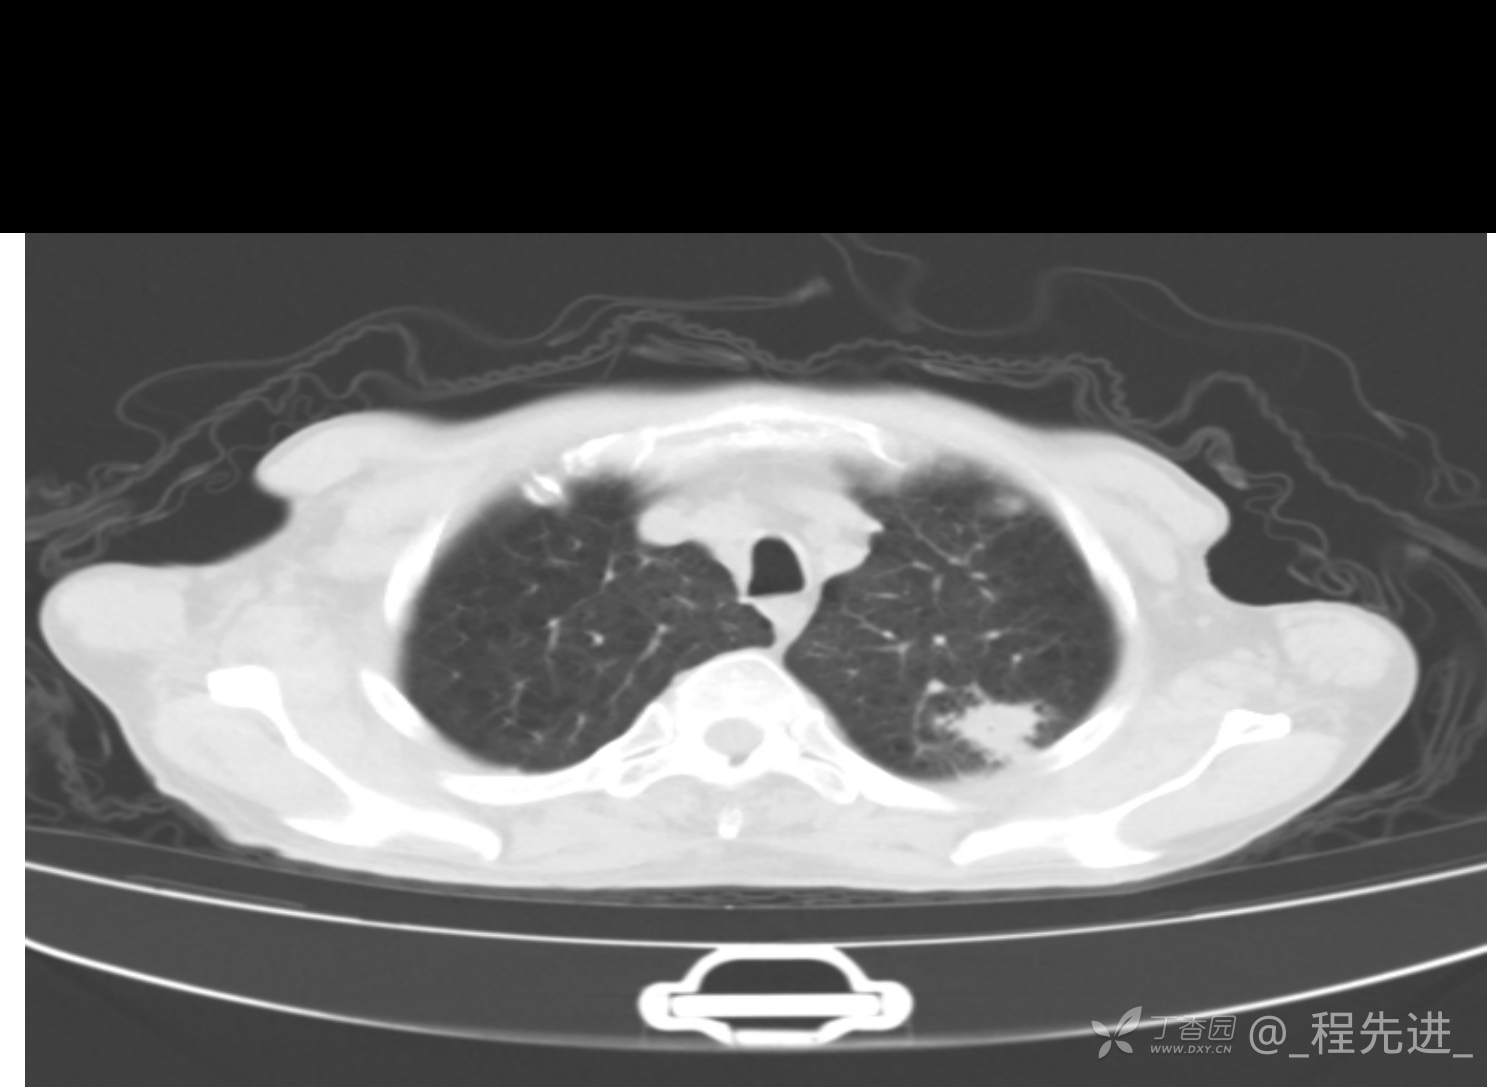

患者性别:男

患者年龄:81岁

简要病史:反复咳嗽、咳痰20余年,加重1周。两肺呼吸音低,可闻及散在干湿啰音。